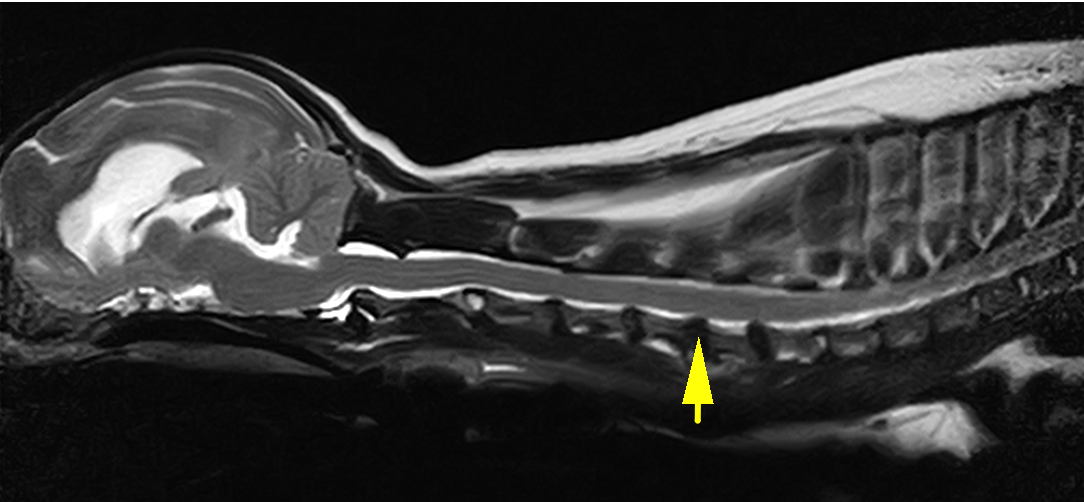

頚部椎間板ヘルニアは頚椎という首の骨をつなぐ椎間板物質が背側に飛び出してしまうことで、そこの神経を圧迫し、疼痛や麻痺を引き起こす疾患です。診断は触診や神経学的検査、レントゲン検査に加え、MRI検査が必須となります。

矢印の部分の椎間板物質が飛び出しているのがわかります。診断名は第5−6頚部椎間板ヘルニアです。

術後のフォローアップMRIです。術前のMRIで突出していた椎間板物質は取り除かれ、スムースになっているのがわかります。